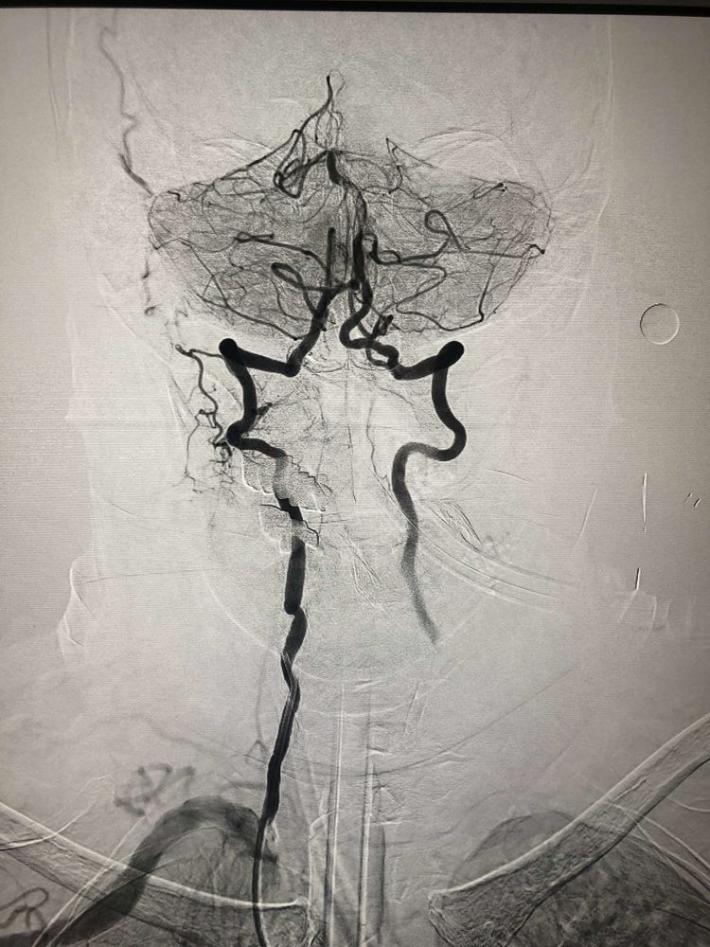

入院后75min,股动脉穿刺成功,后循环造影及右侧颈内动脉正侧位。

导丝导管通过闭塞部位,经微导管造影,证实在远端真腔内,取栓后M1重度狭窄,球囊扩张。

球囊扩张

支架植入术后前向血流通畅